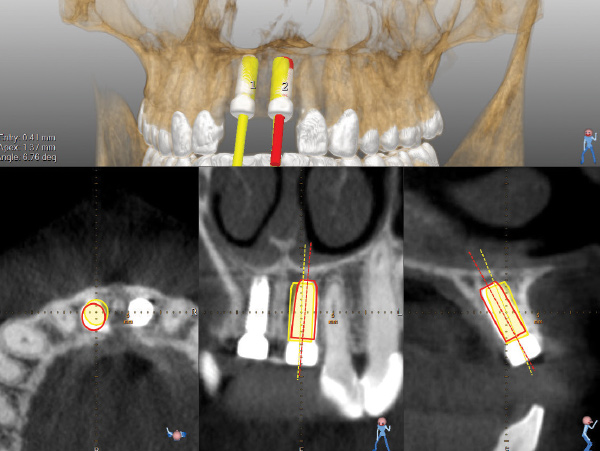

A post-placement CBCT scan was secured and compared to the preoperative CBCT plan using software inherent to the dynamic navigation system (Figure 11). Accuracy results from this case (preoperative plan compared to post-implant placement) were as follows: entry point deviation was 0.13 mm for tooth position No. 8 and 0.41 mm for No. 9; angle discrepancy was 4.3 degrees for No. 8 and 6.76 degrees for No. 9; implant apex depth deviation was 1.10 mm for No. 8 and 1.37 mm for No. 9.

Fig 4. Planning software is shown. STL file of the maxillary arch has been imported from optical scanning and matched to regional anatomy for soft-tissue visualization. The aluminum fiduciary of the CT marker can be observed in the axial view. Virtual teeth have been constructed for Nos. 8 and 9, and the case has been planned for prosthetically directed implant placement on a dynamic navigation platform.

Figure 4

Fig 11. Pre- and post-placement CBCT scan matched with DICOM data and accuracy evaluation for site No. 8. Yellow outlines of implant represent the planned implant position, while red outlines show the actual implant position outcome.

Figure 11